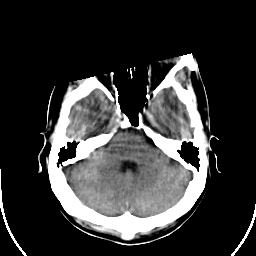

Sarcoma: Roentgen-ray CT -- Slice #6

[Home][Help][Clinical] Slice 6